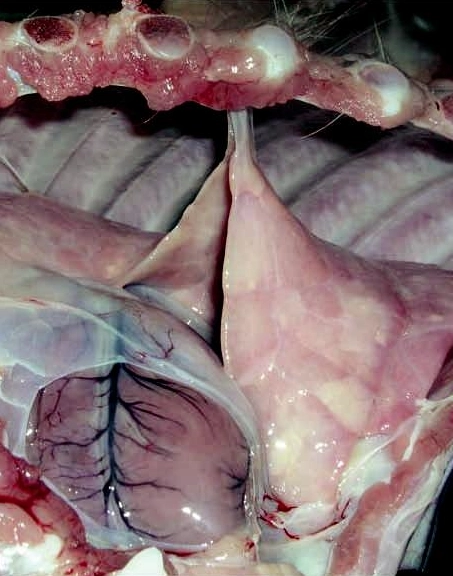

Hình ảnh bệnh tụ huyết trùng ở lợn

- Viêm màng phổi dính vào sườn